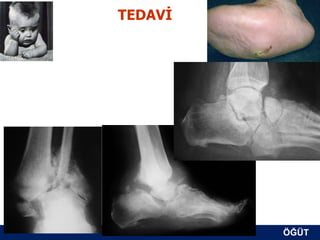

TEDAVİ

ÖĞÜT

KONSERVATİF TEDAVİ

1) Total kontakt alçılama             2 – 3 ay

2) Yürüme botu                        2 – 3 ay

+Bifosfonat ?

Akut dönem geçince (3. EVREDE) kalıcı olarak yük

vermeye izin verilir (derin ayakkabı, AFO, PTB)